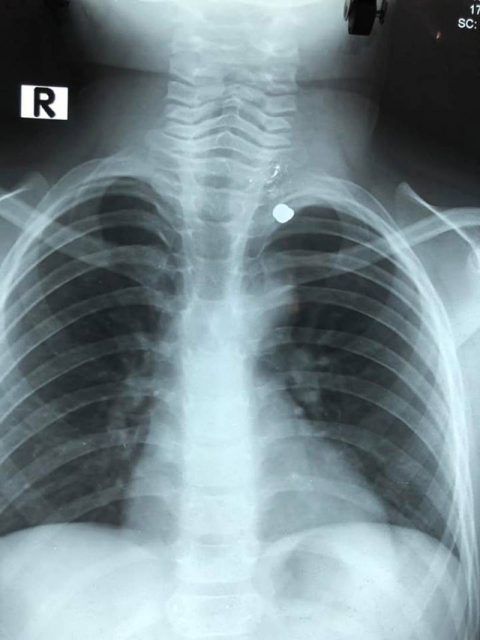

Qua thăm thăm khám, chụp X-Quang, các bác sĩ phát hiện một viên đạn xuyên từ cổ xuống ngực bé M.H. May mắn là đạn đi từ cổ đến đỉnh phổi trái nhưng không xuyên vào mạch máu lớn, khí quản hay tim.

Hình ảnh chụp X-quang cho thấy vị trí của viên đạn. (Ảnh: VTV)